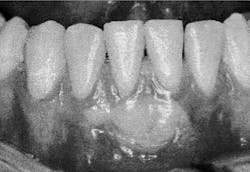

The depth of the dimension includes connective tissue, possibly osseous tissue, and epithelium. The presence of a bony plate will increase this dimension. The osseous crest is typically 1 to 2mm apical to the cementoenamel junction. Two variations of lingual or facial bone position are dehiscences and fenestrations. When the bone dips down more than 2mm from the cementoenamel junction, a dehiscence is formed. In photograph #2, the osseous defect on the buccal aspect of tooth #21 is an example of a dehiscence. If a thinning in the bone creates an aperture or window to the tooth surface, it is a fenestration.

Clinically, it is common to see mucosa becoming more inflamed in the presence of plaque than gingival tissues. Patients often may experience difficulty brushing areas where there is no zone of attached gingival tissue. Inflamed mucosal tissues can result in significant discomfort, inhibiting patients from proper maintenance of the area. In photograph #2 the character of the soft tissue on the facial aspect of tooth #25 presents a case demonstrating this situation. A 25-year-old patient presented with significant discomfort, no attached gingival tissue, and inflamed mucosa. The patient reported great difficulty maintaining the area.

Photograph 2: Dehisence, tooth #21